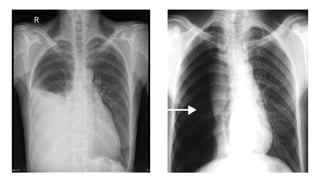

This document discusses key aspects of thorax radiology including positioning for PA and AP views, assessing heart size, visibility of anatomical structures like the scapulae, lungs zones, and measurements like cardiothoracic ratio. It provides guidance on evaluating rotation, inspiration, and penetration on chest x-rays as well as identifying structures like the lobe of azygos vein and aortic knuckle.